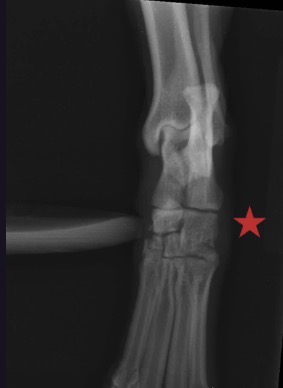

What view is this? When stress is applied, which joint opens up? Is this joint stable or unstable?

DP view of tarsus

Stress applied to open up lateral side of the joint → distal intertarsal joint visible

No instability seen on this side of the joint